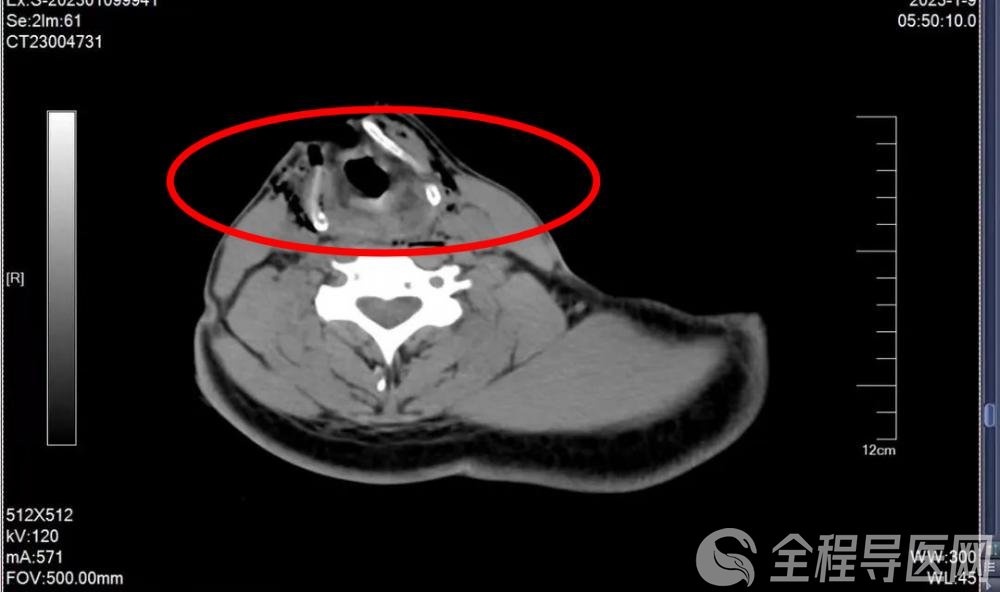

患者术前影像资料

深达喉腔!

喉室暴露!

伤口距颈主动脉仅1cm!

会厌根部离断!

左甲状软骨板上缘见游离软骨,甲状舌骨肌完全离断!

胸部3处伤口,两处深达剑突!腹直肌全层断开!一处进入胸腔!